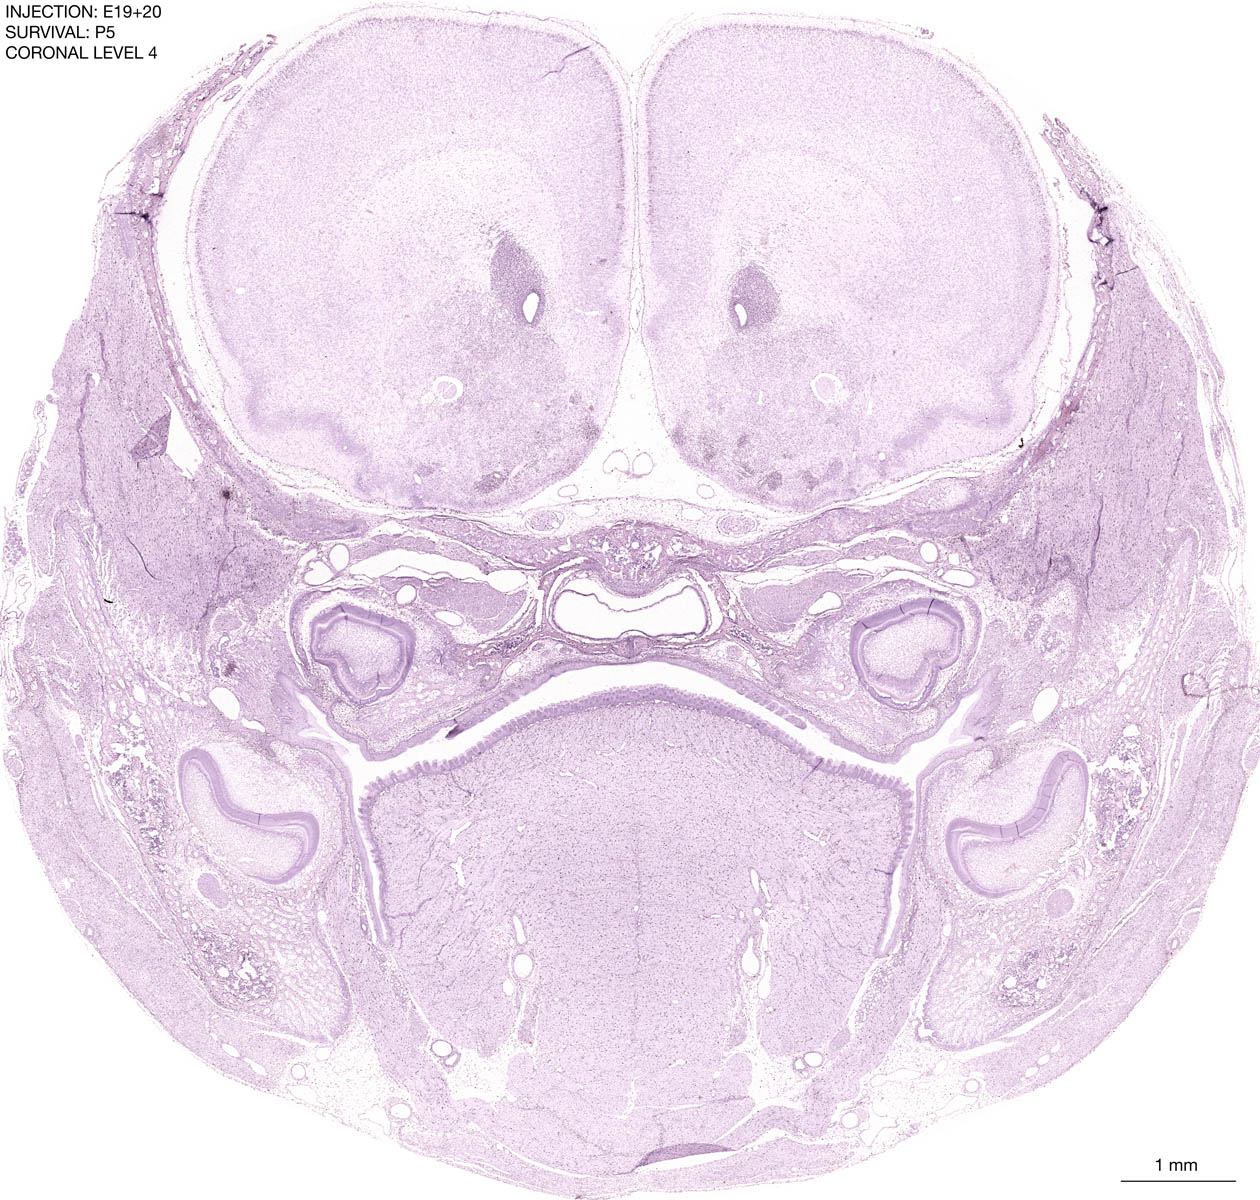

E19+20 P5 Survival The images below are from the brain of a rat that was exposed to tritiated thymidine on E19+20 and survived to P5. Download: Large | High Res Download: Large | High Res Download: Large | High Res Download: Large | High Res Download: Large | High Res Download: Large | High Res Download: Large | High Res Download: Large | High Res Download: Large | High Res Download: Large | High Res Download: Large | High Res Download: Large | High Res Download: Large | High Res Download: Large | High Res Download: Large | High Res Download: Large | High Res Download: Large | High Res Download: Large | High Res Download: Large | High Res Download: Large | High Res Download: Large | High Res Download: Large | High Res Download: Large | High Res Download: Large | High Res Download: Large | High Res Download: Large | High Res Download: Large | High Res Download: Large | High Res